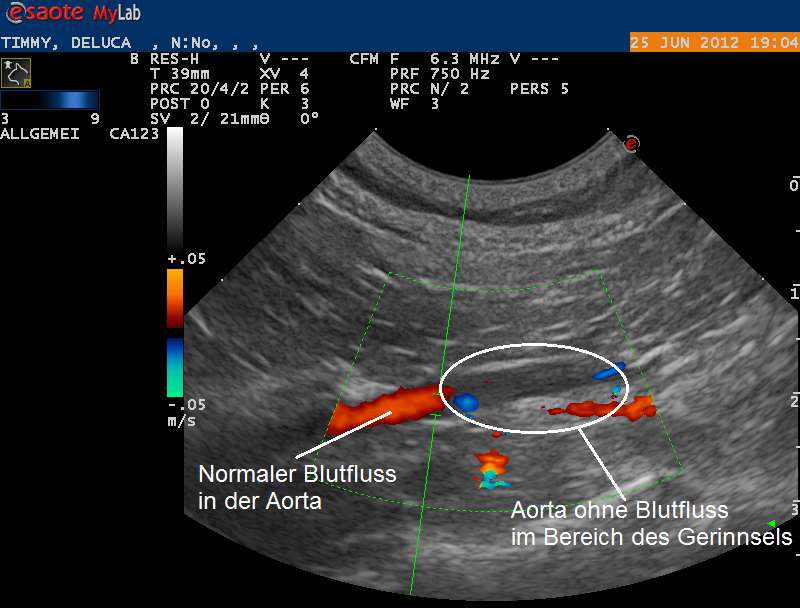

Nun wird die Körperschlagader mittels Ultraschall genauer untersucht. Diese zweigt sich vor dem Beckeneingang unter anderem in die beiden Schenkelarterien auf und versorgt so die Gewebe der Hinterbeine mit Sauerstoff. Eine Doppler-Ultraschalluntersuchung zeigt, dass die Körperschlagader nicht mehr komplett durchgängig ist und nur noch sehr wenig Blut die Beinarterien erreicht. Beim Doppler-Ultraschall kann fliessendes Blut farbcodiert dargestellt werden und so Hindernisse in einem Gefäss dokumentiert werden.

Die beiden Schenkelarterien werden mittels Ultraschall ebenfalls lokalisiert - sie zeigen aber aufgrund der Blockade in der Körperschlagader wie befürchtet nur einen sehr geringen Blutfluss.

Unsere Untersuchungen haben den Verdacht bestätigt, dass Timi an einer Embolie (Gefässverschluss) der Körperschlagader-Aufzweigung im Beckenraum leidet. Aufgrund der schweren Herzerkrankung hat sich im Herzen ein Blutgerinnsel gebildet, welches über die Körperschlagader in den Kreislauf gepumpt wurde und nun die Aufzweigung der Schlagader blockiert - ein sogenannter Sattelthrombus ist entstanden.